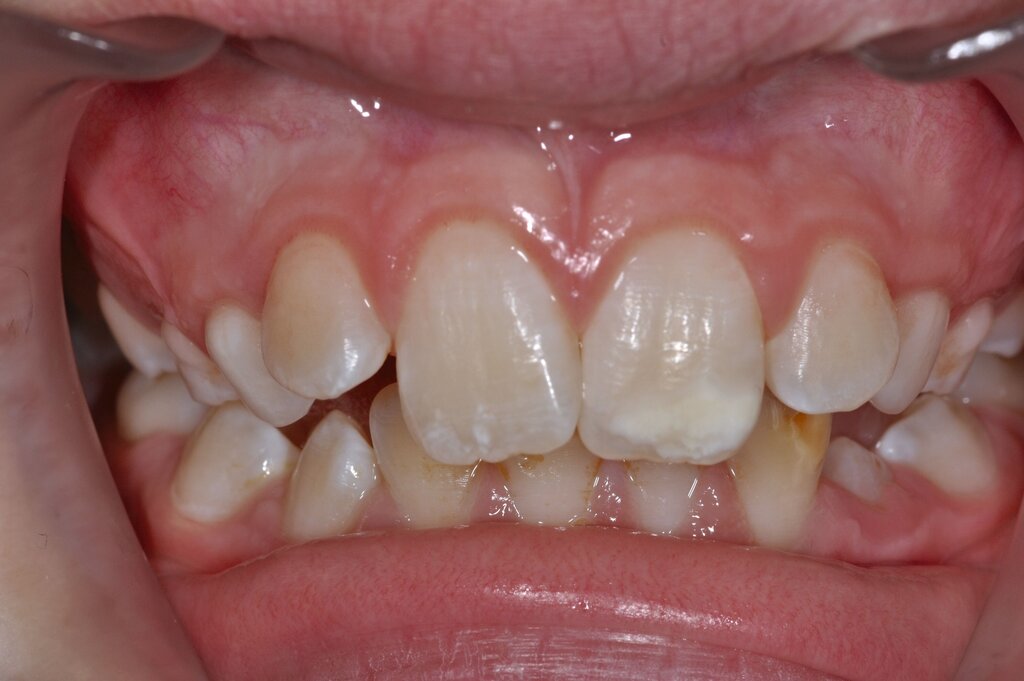

Bereits 2003 unterteilte die European Academy of Paediatric Dentistry (EAPD) die Erkrankung nach dem Schweregrad, da dieser wesentlich die Art der Versorgung beeinflusst. Dabei wurde zwischen umschriebenen Opazitäten, posteruptiven Schmelzeinbrüchen und sogenannten atypischen Restaurationen an den Schlüsselzähnen der MIH (Sechsjahrmolaren und bleibende Frontzähne) unterschieden [Weerheijm et al., 2003].

Diese Klassifikation dient als Grundlage für die Therapieempfehlungen. Deutlich wird, dass aufgrund der Symptomatik die Therapie der Zähne höchst unterschiedlich ausfällt. Dass etwa eine Opazität ohne Überempfindlichkeit (Index 1, Abbildung 1) ein anderes therapeutisches Vorgehen erfordert als ein Zahn mit nahezu komplettem Einbruch der Zahnoberfläche und mit Hypersensitivität (Index 4, Abbildung 2), ist offensichtlich.

Für die zahnärztliche Praxis gibt die Einteilung eine Orientierung darüber, welche Behandlungsmaßnahmen erforderlich sind beziehungsweise eingesetzt werden können. Je nach Schweregrad wird dabei zwischen nichtinvasiven und invasiven Maßnahmen sowie einer kurzzeitigen oder längerfristigen, restaurativen Therapie unterschieden. Bei der Überarbeitung des Konzepts wurde zudem zwischen Front- und Seitenzähnen differenziert (Abbildung 3) [Bekes et al., 2023; Steffen et al., 2017].